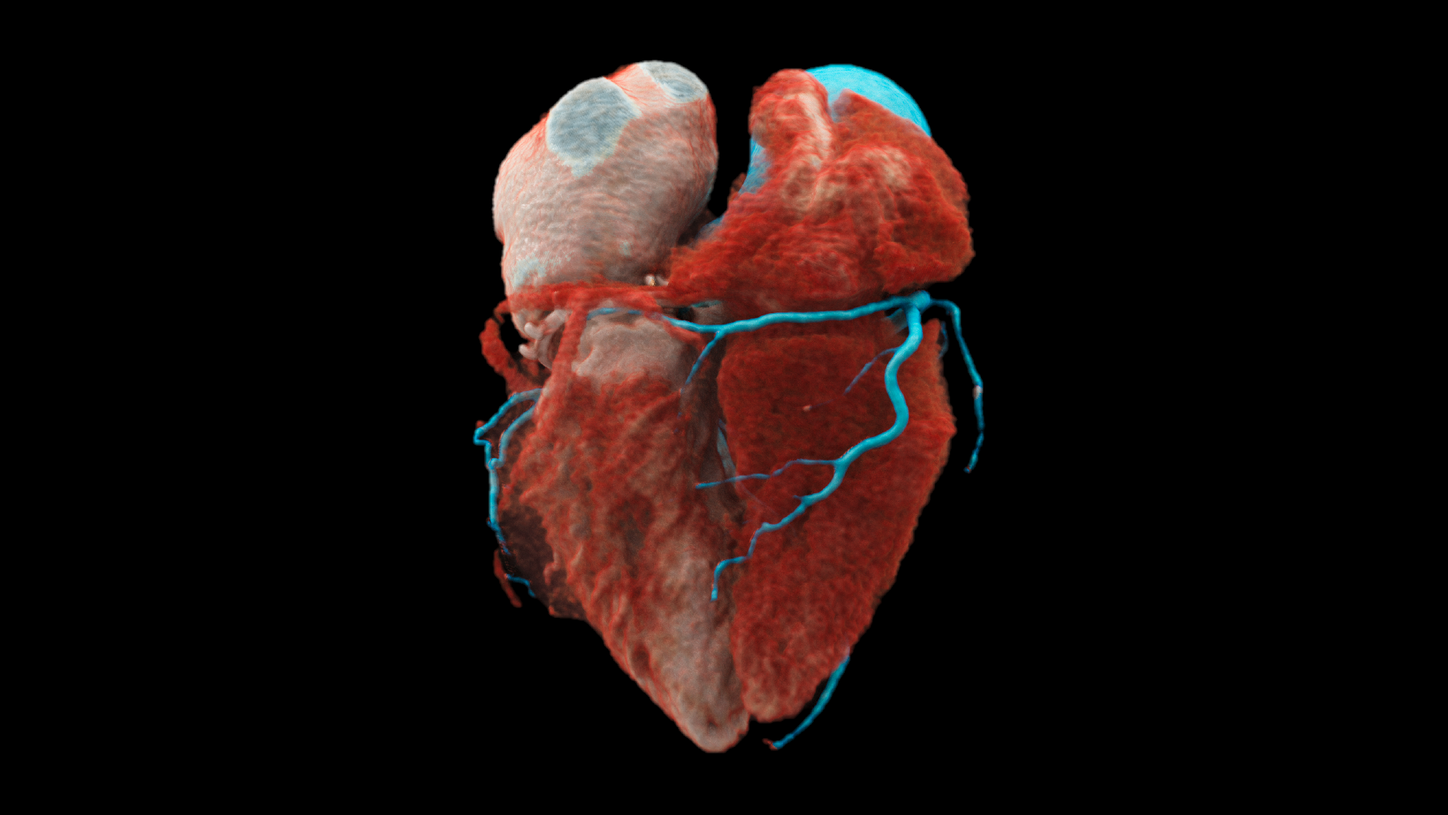

At the heart of NAEOTOM Alpha® is a radically new photon-counting detector. The QuantaMax detector directly converts X-rays into an electrical signal, which is then used to create an image. The energy of each X-ray is measured, so spectral information is available for every scan, and the images are contrast-rich with high spatial resolution at the same dose. Combining the high spatial resolution of the QuantaMax photon-counting detector with our Dual Source temporal resolution enables the visualization of fine details for increased diagnostic confidence.

The unique Dual Source technology enables a native temporal resolution of 66 ms and a scan speed of up to 74 cm/sec – mastering even the most challenging imaging tasks.